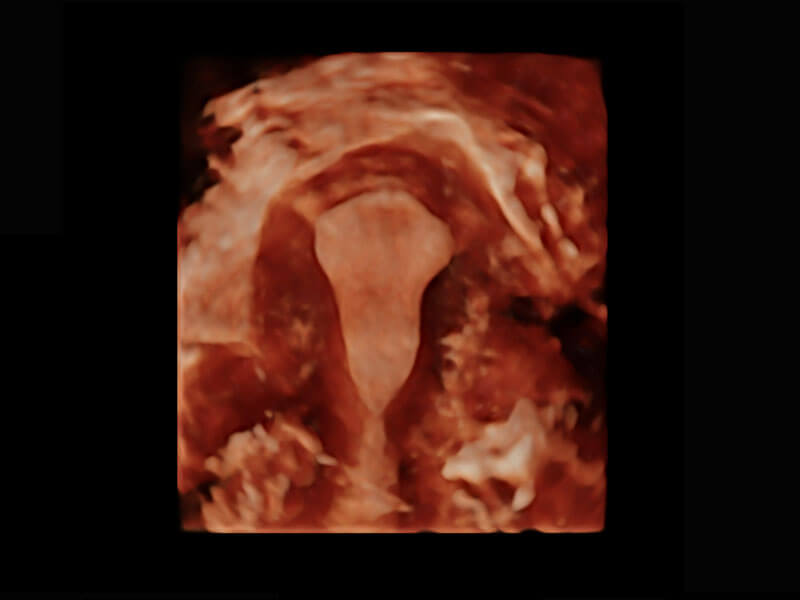

• 腔内三维-宫内节育器

• 腔内三维-光影成像

P60搭载一系列胎儿心脏成像技术,实现精细的胎儿心脏评估。

• 右室双出口

• 胎心容积成像